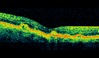

AMD. High resolution horizontal and vertical scans showing cystoids oedema, CNV, RPE proliferation and sub retinal fluid at the fovea.